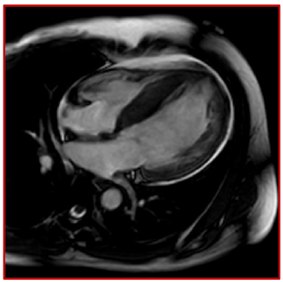

She provided a history of atypical chest pain, exertional shortness of breath, and occasional palpitation on further assessment—no lower limbs edema or syncope. Physical examination was utterly unremarkable. ECG (Figure 1) revealed brad ectopic pacemaker rhythm in lower atrial focus, Q waves in inferior leads with R wave in V1-V2, and nonspecific ST-T changes. Transthoracic echocardiography with contrast (TTE) revealed a thickened LV with more than three trabeculations protruding from the posterolateral wall. These moved synchronously with the myocardium (Figure 2). Intertrabecular recesses were evident, and the systolic function was moderately reduced (LV ejection fraction, 0.37), with a thick basal-mid septum of 1.9cm. The rest of the LV wall is hyper-trabeculated (Figure 2). Cardiac MRI showed thick basal-mid septum (1.9cm), hyper trabeculated LV with Peterson et al. criteria of 2.5 in keeping morphically with the diagnosis of LVNC. A patchy diffused mid-wall myocardial enhancement from base to apex was noticed indicates myocardial fibrosis. No cardiac thrombi were appreciated (Figure 3).

Figure 3 Suboptimal CMR, however; it showed thick basal-mid septum (1.9 cm), hyper-trabeculated LV, and patchy diffuse enhancement from base to apex indicative of myocardial fibrosis.

The diagnosis of LVNC is challenging; in one series, the diagnosis of LVNC was initially missed in 89% of the cases: 42% of the cases were dilated cardiomyopathy, and 15% were hypertrophic cardiomyopathy.15 Isolated LV noncompaction is diagnosed by cardiac imaging, the TTE, and cardiac magnetic resonance (CMR). However, contrast echocardiography, 3-dimensional echocardiography, transesophageal echocardiography, multidetector computed tomography, and LV angiography might reveal the deep intertrabecular recesses and help in the diagnosis.16–18 Prominent trabeculations of the left ventricle can be found in up to 68% of the general population, which is considered a normal variant.18 The anatomic distribution of the trabeculations can be a helpful criterion for the diagnosis in that group because the trabeculations course from the free wall to the ventricular septum in 85% of LVNC cases (Figure 3).18